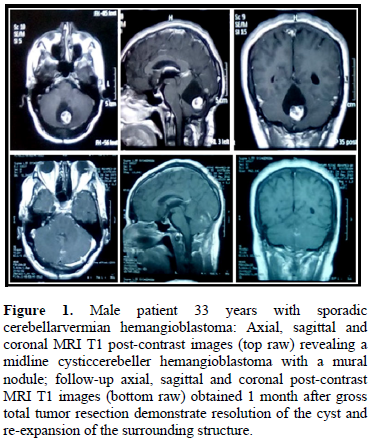

Preoperative embolization was not performed in any of the cases enrolled in our study. Lateral Suboccipital approach was applied in 17 procedures (77%) and midline suboccipital approach was applied in 5 procedures (23%). Gross total microsurgical resections were achieved in 18 operations (82%) (Figure 1). Partial microsurgical resections were performed in 4 lesions (18%) because massive tumor bleeding was encountered intraoperatively and tight adhesion between the tumor and surrounding tissues. Six patients underwent adjunctive ventriculoperitoneal shunting due to associated secondary

hydrocephalus. The mean blood loss reported was 660 ±450 ml.